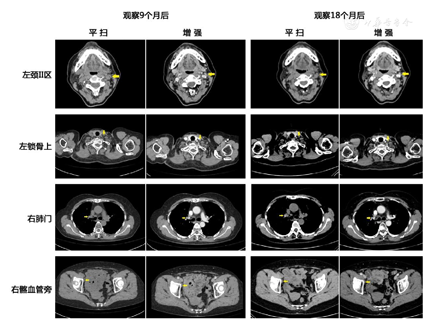

患者分别于随诊9个月及18个月后复查增强CT,提示左颈Ⅱ区淋巴结逐渐缩小,其他淋巴结(左锁上、右肺门、双侧髂血管旁等等)未见明显变化(图2)。患者无明显不适。根据随诊情况,考虑患者全身浅表淋巴结为反应性增生可能性大,嘱患者长期规律随诊。